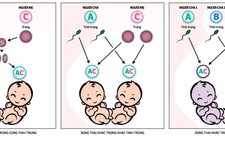

Dự án tổng hợp bộ gen người nhân tạo được công bố vào đúng thời điểm những tranh cãi căng thẳng đang diễn ra liên quan tới vấn đề đạo đức, khi sử dụng kỹ thuật chỉnh sửa gen người CRISPR-Cas9 trong các phôi thai người.

Tranh cãi này dấy lên sau sự việc năm ngoái, các nhà khoa học Trung Quốc công bố kết quả nghiên cứu liên quan tới việc sử dụng nó với phôi thai người. Sự việc khiến cộng đồng quốc tế đồng loạt phản đối, yêu cầu cấm triệt để những nghiên cứu dạng đó.

Những người ủng hộ thì nói kỹ thuật CRISPR có thể giúp giới khoa học mau chóng tìm ra cách thức khắc phục và phòng ngừa bệnh di truyền.

Trong khi đó, phe phản đối lo ngại các hậu quả khôn lường xảy đến với những thế hệ mới bị áp dụng kỹ thuật này. Chưa kể mối lo các bậc cha mẹ vì quá mong muốn con cái xuất sắc mà chủ động nhờ các chuyên gia di truyền nhúng tay vào bản đồ gen của con cái họ từ khi còn trứng nước.